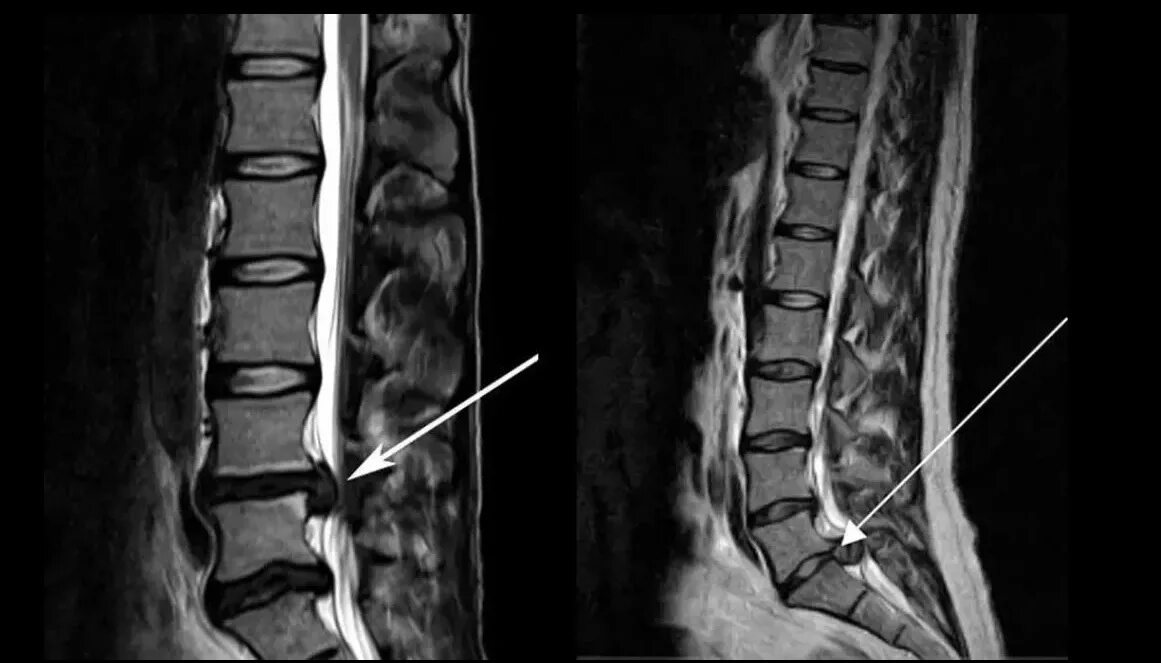

Как выглядит грыжа поясничного отдела позвоночника